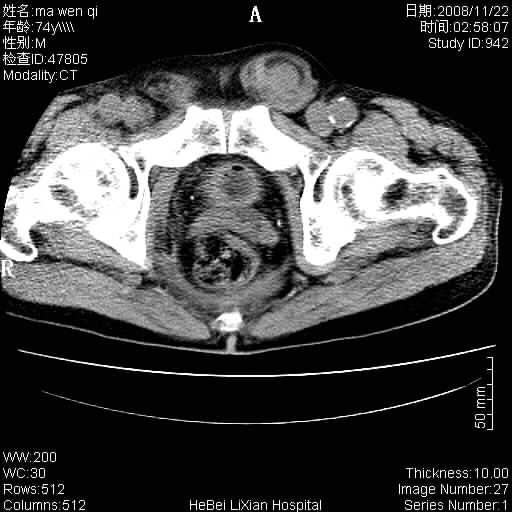

患者男 74岁.突然昏迷,休克6小时.血压70/30,头颅ct未见异常,既往体健.

补充病史,保留导尿10小时,尿袋内只有少许尿液,患者于住院后15小时后去世.

腹主动脉、双侧髂动脉夹层动脉瘤破裂出血进入腹腔。

考虑双侧髂a瘤,伴破裂出血

腹主动脉、双侧髂动脉夹层或动脉瘤破裂出血进入腹腔

1)考虑双侧髂动脉瘤并右侧动脉瘤破裂出血,右侧腹膜后及腹腔积血。2)双侧腹股沟疝。

支持(1)双侧髂动脉瘤并右侧动脉瘤破裂出血,右侧腹膜后及腹腔积血。(2)双侧腹股沟疝。

1)考虑,腹主动脉、双侧髂动脉夹层动脉瘤破裂伴右侧腹膜后及腹腔积血。2)双侧腹股沟疝。

1)考虑胸、腹主动脉、双侧髂动脉瘤并右侧动脉瘤破裂出血,右侧腹膜后及腹腔积血。2)双侧腹股沟疝。